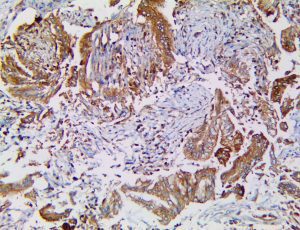

It is the ICU physician who is most likely to witness one of the deadliest manifestations of the abnormal immunological response, the cytokine storm syndrome (CSS). This response is also referred to by some as the cytokine release syndrome (CRS). CSS is characterized by continuous activation and expansion of macrophage and lymphocyte populations, which secrete large amounts of cytokines, causing the cytokine storm. This massive cytokine release is akin to hemophagocytic lymphohistiocytosis (HLH) disease, a syndrome characterized by initial unchecked and persistent activation of cytotoxic T lymphocytes and NK cells.

Clinical and laboratory manifestations of HLH include fever, enlarged liver and/or spleen, neurologic dysfunction, coagulopathy, liver dysfunction, cytopenias (i.e., low levels of erythrocytes, leukocytes, and/or platelets), hypertriglyceridemia, hyperferritinemia, hemophagocytosis, and eventually diminished NK cell activity as the immune system becomes progressively paralyzed. HLH can be familial (primary HLH) or secondary to another disease process (sHLH), such as rheumatic disease, in which it is referred to as macrophage activation syndrome (MAS, characterized by elevated ferritin).

This activation induces inflammatory monocytes to highly express IL-6, starting a localized and then systemic cascade effect that results in hyperproduction of IL-6, which accelerates the inflammatory process. Because IL-6 also increases vascular permeability, excessive levels cause blood vessels to become very leaky. This, along with clotting factors released from vascular endothelial cells, stimulates the coagulation cascade, resulting in microthrombosis (tiny clots), which leads to ischemia and tissue death of the kidney, intestines, heart, liver, brain and extremities.